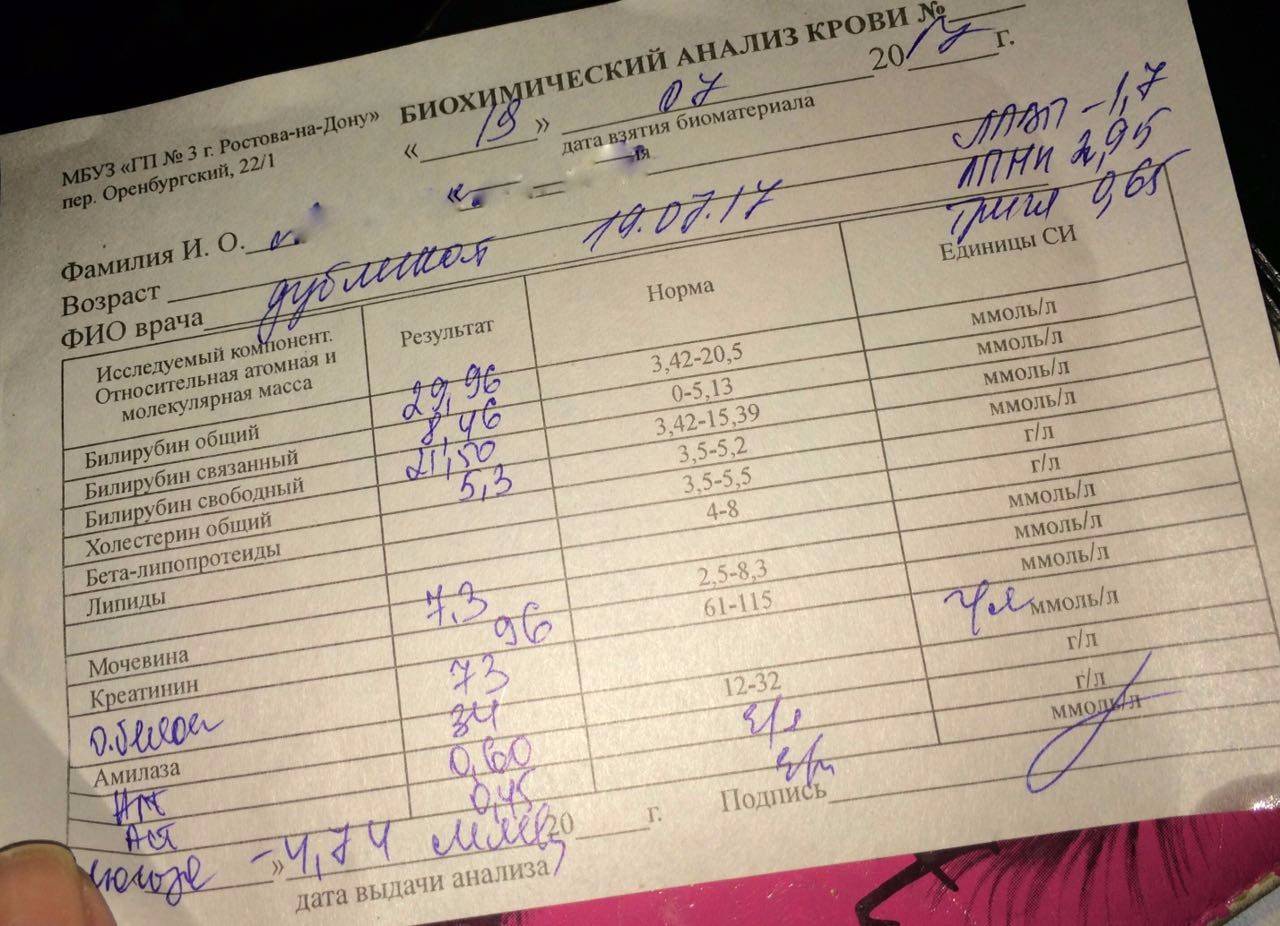

Почки играют важную роль в фильтрации крови и удалении отходов из организма.

Причинами почечной недостаточности могут быть различные заболевания, травмы или генетические факторы.

Симптомы почечной недостаточности могут включать отеки, повышенное давление и изменение цвета мочи.